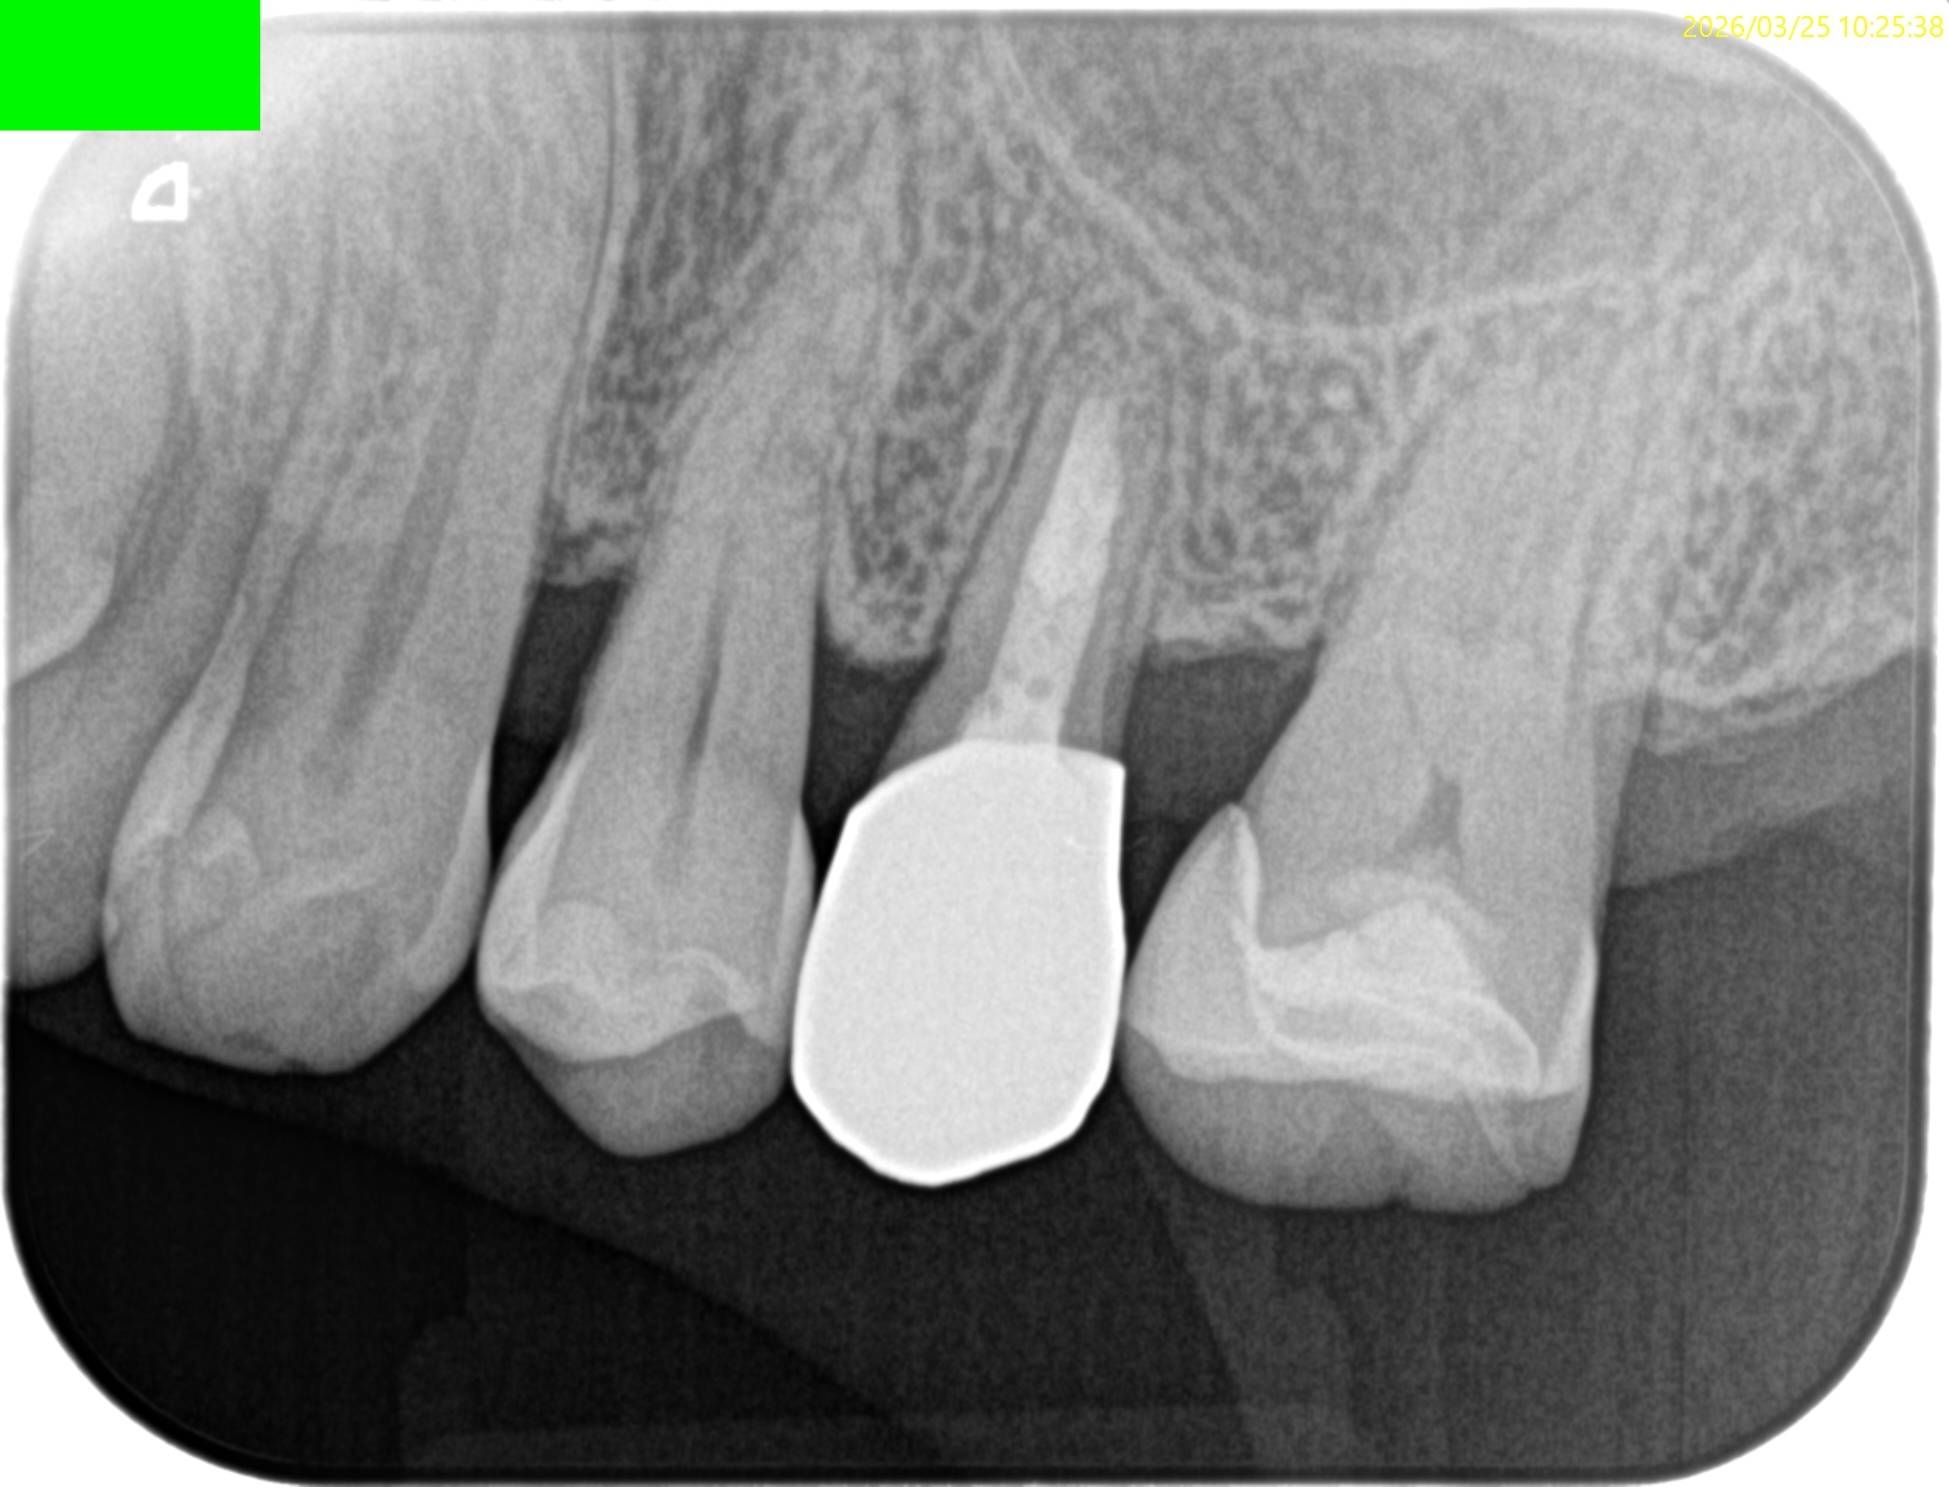

#13 Apicoectomy 1yr recall(2026.3.25)

1年前と比較してみた。

根尖病変は消失し、外科治療に関わる骨欠損も完治した。この状態ならセラミックに変えてもいいだろうが、術前の状態では無理である。